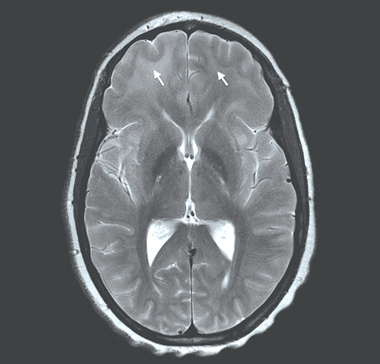

Persistent status epilepticus necessitated treatment with loading doses of phenytoin, sedation and intubation. Magnetic resonance imaging (MRI) of the brain showed extensive areas of uniform high signal intensity within the supratentorial white matter and mild meningeal enhancement (Box 1). Meningoencephalitis was diagnosed, and the patient was treated with ceftriaxone and aciclovir. Based on history, presentation and cerebrospinal fluid findings, she was also given isoniazid, rifampicin, ethambutol, pyrazinamide, pyridoxine and dexamethasone for suspected tuberculous meningoencephalitis. Multiple investigations for bacterial, viral and fungal pathogens, including serological tests for HIV, and polymerase chain reaction (PCR) tests and culture for Mycobacterium tuberculosis, gave negative results (Box 2).

MRI findings in trypanosomiasis are non-specific, ranging from meningeal enhancement in earlier CNS disease to bilateral confluent hyperintense T2 signals in the subcortical white matter in late disease, as seen in our patient.7 Although not diagnostic, MRI is a useful adjunct in supporting the diagnosis as relatively few conditions cause this distinct MRI appearance, including acute disseminated encephalomyelitis, cerebral gliomatosis, the leukodystrophies and lymphoma, all of which were considered in our patient.